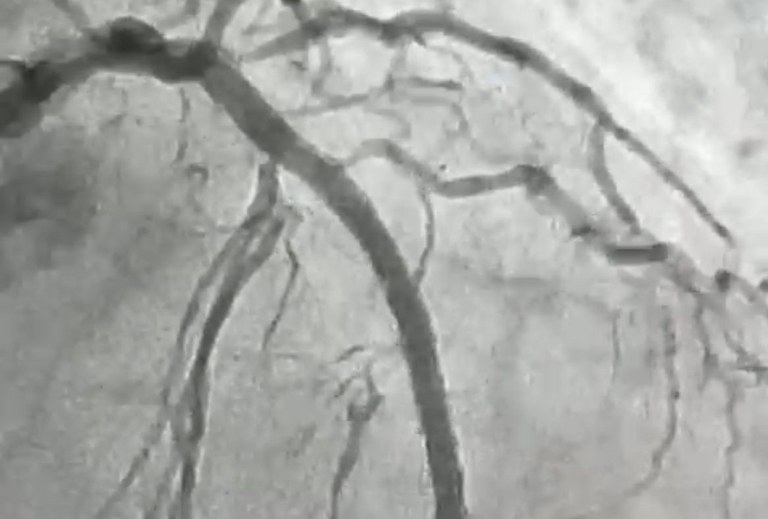

O procedimento foi realizado em uma paciente de 84 anos, moradora de Itaporanga, que apresentava uma lesão grave e altamente calcificada na artéria descendente anterior, considerada a principal artéria do coração. Segundo o cardiologista intervencionista, Jeann Santiago, um dos médicos responsáveis pela realização do procedimento, a condição exigia um tratamento extremamente delicado, com risco elevado, devido à dureza da placa obstrutiva, comparada pelos médicos a uma “pedra” no interior do vaso.

“Para possibilitar a abertura da artéria, a equipe utilizou a aterectomia rotacional, técnica que funciona como uma microfuradeira capaz de desgastar e desobstruir placas de cálcio muito rígidas. Em seguida, com o auxílio do ultrassom intravascular, foi possível medir com precisão a extensão da lesão e determinar o tamanho ideal dos dispositivos a serem implantados. Após a preparação do vaso, foram colocados dois stents farmacológicos, completando o processo de revascularização”, explicou o cardiologista.